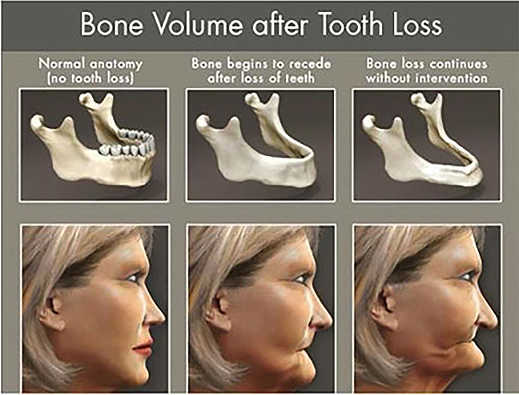

What Happens if a Missing Tooth is Not Replaced?

Tooth loss affects your ability to speak and eat properly, collapse your facial profile changing the shape of your face, and making you appear older.